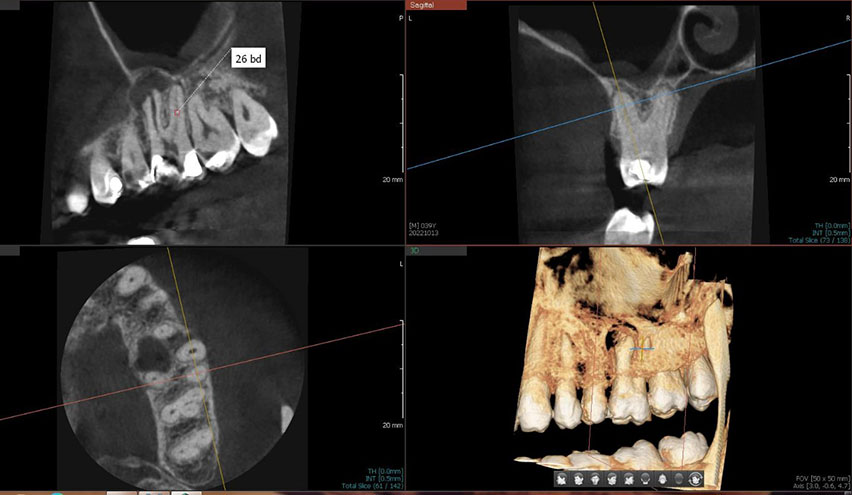

Oralna hirurgija je posebna i kompleksna grana stomatologije koja podrazumijeva kombinaciju različitih hirurških metoda u procesu izliječenja zuba.

Oralna hirurgija zahtijeva visoku preciznost u radu te stručnost osoblja koje izvodi zahvat.

Naša ordinacija i sala ispunjavaju najstrožije kriterije iz ove oblasti stomatologije. Posjedujemo opremu najnovnije generacije, a naš stručni tim je prošao sve procese i obuke te smo certificirani za obavljanje i najkompleksnijih zahvata.

Every complicated process that includes more different treatments to be solved is considered under oral surgery.

Our ambulance is equippted by best and high quality technology, materials and well recognized specialists from Bosnia and Herzegovina and region are doing any kind of procedure needed.